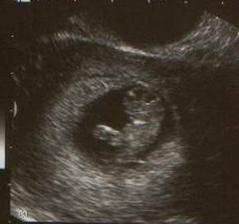

krasny vztah,snazilkovanie, //, choroba z minulosti, UPT,koniec vztahu....

aj takmer 4mesiace po odchode do nebicka mi moje bábetko chyba...